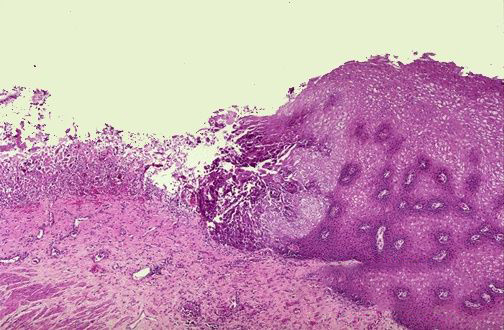

病理改变主要在胆囊黏膜上皮细胞的基底膜内有胆固醇沉积,组织细胞过度膨胀,形成黄色小结节,有细蒂与胆囊相连。有两种类型:一是弥漫型,结节布满胆囊,典型者形似草莓,病理上称为“草莓样”胆囊;另一种为局限性隆起,单个或多发,形如息肉。多发生于体部和颈部,直径多小于1cm,体积增长缓慢,质脆,容易脱落,在多种成核因素作用下,形成结石。